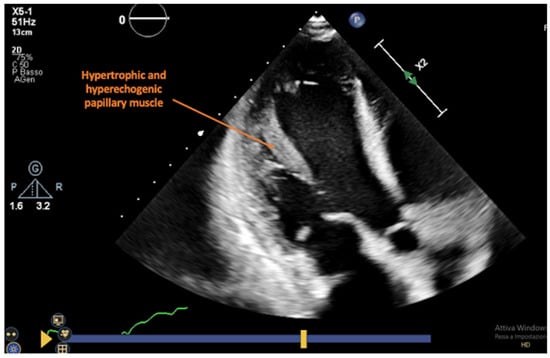

| Ciliberto et al. [39] | Increased LV mural thickness and mass, reduction in LV EF, RV dilatation and wall motion impairment, pericardial effusion, increased myocardial echogenicity | 21 | NA | 89 with 1 parameter 72 with ≥2 | 90 with 1 parameter 100 with ≥2 | NA |